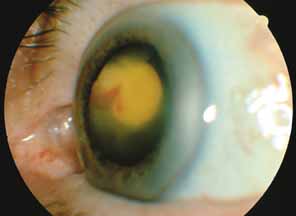

The majority of cases of ghost cell glaucoma occur following vitrectomy for diabetic retinopathy, vitreous hemorrhage due to trauma, or vitreous hemorrhage following anterior segment surgery (i.e., cataract extraction or corneal transplant). Although studies suggest that a disruption of the anterior hyaloid face may be a necessary precedent, ghost cell glaucoma probably can occur with an intact hyaloid if a sufficient quantity of vitreous blood is present.27 The clinical presentation includes acute pressure elevation, corneal edema, and lack of keratic precipitates. Minute tan cells (ghost cells) may layer out, producing a pseudohypopyon or, if admixed with blood, a “candy-striped” hypopyon. (Fig. 3) Intraocular pressure elevations after diabetic vitrectomy raise concerns regarding concomitant neovascular glaucoma. However, neovascular glaucoma rarely develops in the immediate postvitrectomy period, unless some anterior segment neovascularization was present preoperatively. Late-onset pressure elevations (> 6 to 8 weeks out) in a postvitrectomized diabetic eye usually signal neovascular glaucoma.